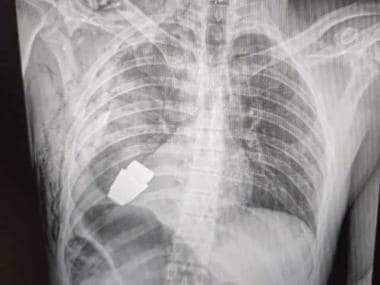

New Delhi: A Ukrainian soldier got a new lease of life when an unexploded VOG grenade was surgically removed from his Chest, just under his heart.

Ukrainian army surgeons undertook the risky operation to the remove the still explosive grenade from the soldier body, with the help of two soldiers who looked over his safety.

“Our military doctors conducted an operation to remove a VOG grenade, which did not break, from the body of a soldier.The operation lasted in the presence of two sappers who supervised the safety of the medical staff and the patient”, the General Staff of Ukrainian Armed Forces of Ukraine wrote on Facebook.

Since the explosive was live and there were chances of an explosion, the doctors operated the soldier without electrocoagulation, a procedure that uses electric current to stop blood flow during the surgery.

These grenades explode when they hit something hard, but since it could pierce through the soldiers chest it didn’t explode and remained live, just underneath his heart, till it was very carefully removed.